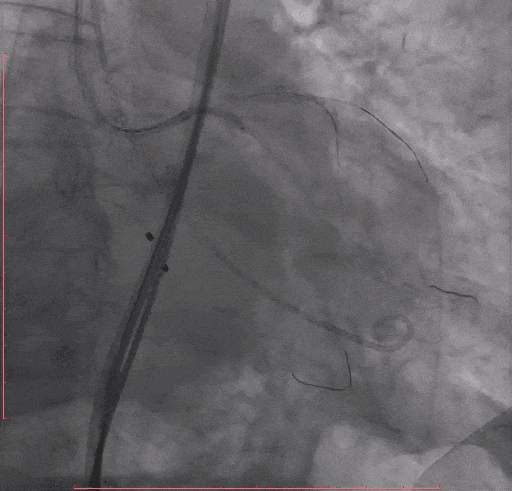

Step 6.主动脉瓣球囊预扩张

Step 7. Taurus 26 瓣膜释放至工作位造影确认位置